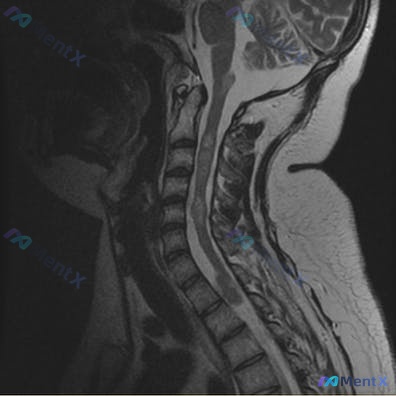

影像:颈椎MRI提示生理曲度变直,C4/5-C6/7椎间盘突出、椎管狭窄,C4-C7水平脊髓内见长T2高信号影。